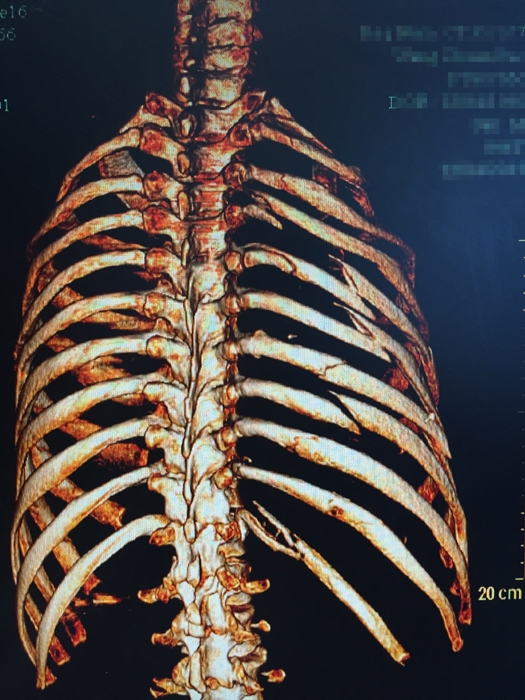

??? 說起張成的經(jīng)歷,讓人唏噓不已。2015年12月4日,46歲的張成不慎從四層高樓墜落,當(dāng)場(chǎng)不省人事。家人立即將張成送入當(dāng)?shù)蒯t(yī)院搶救,經(jīng)檢查發(fā)現(xiàn)張成血?dú)庑?,?chuàng)傷性濕肺,全身多處骨折,光肋骨就有11根骨折,右側(cè)股骨骨折,右側(cè)肱骨下段粉碎性骨折,最嚴(yán)重的是還有脾破裂,骨盆骨折和胸椎骨折。因傷勢(shì)嚴(yán)重,當(dāng)?shù)蒯t(yī)院建議家屬將張成轉(zhuǎn)到上一級(jí)醫(yī)院。

患者入院時(shí)的X影像